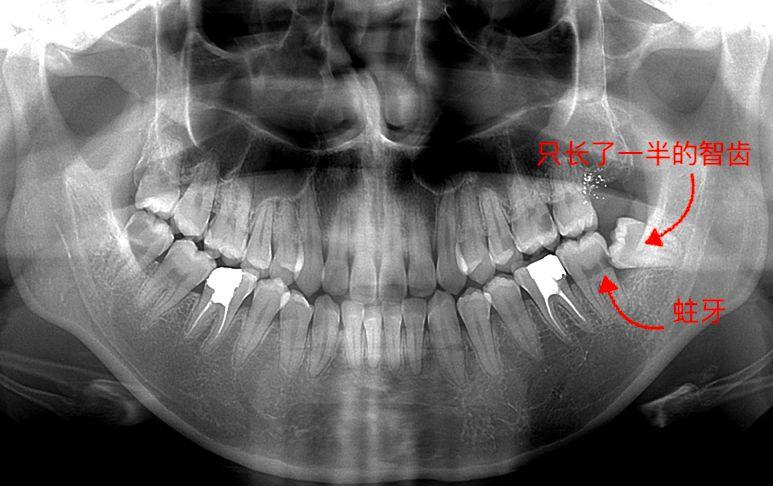

圖一,手指的這顆,很比別的牙矮,沒有長出來是埋伏型的一顆,為什么去拔,因為它其實有頂我旁邊牙齒了,影響我這邊吃東西了,咬東西隱隱作痛,而且只要人不舒服這邊準(zhǔn)發(fā)炎和牙齦紅腫。

牙片,手指著的就是有問題的智齒

▼